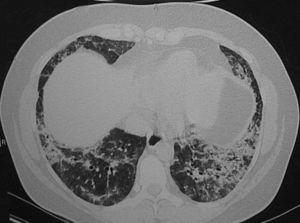

Mujer de 37 años, que ingresó en nuestro servicio por presentar disnea. Era exfumadora de 5 años-paquete y no presentaba ningún otro antecedente patológico de interés. Trabajaba de ama de casa y realizaba alguna tarea en agricultura (cerezos y almendros), pero sin contacto con insecticidas. No presentaba ningún antecedente familiar de interés ni seguía ningún tipo de medicación habitual. Refería contacto con perros, gatos y palomos. Un mes antes del ingreso había comenzado con disnea, que fue progresiva hasta convertirse en disnea de mínimos esfuerzos, sin ningún otro síntoma. En la exploración física destacó la presencia de crepitantes tipo velcro en el tercio inferior de ambos campos pulmonares; el resto fue normal. En la radiografía de tórax se observó un patrón intersticial de predominio en campos inferiores y distribución periférica. La analítica sanguínea mostró una velocidad de sedimentación globular de 37 mm/h; el resto de los parámetros fue normal, incluidos gasometría arterial, enzima conversiva de la angiotensina, hormonas tiroideas, anticuerpo antinuclear y factor reumatoide. Las serologías para los virus de la inmunodeficiencia humana y de la hepatitis C y B fueron negativas, al igual que las precipitinas para antígeno de paloma. La exploración funcional respiratoria mostró los siguientes datos: capacidad vital forzada (FVC) de 1.810 ml (47%), volumen espiratorio forzado en el primer segundo (FEV1) de 1.740 ml, FEV1%/FVC del 116% del teórico, capacidad pulmonar total (TLC) de 2.990 ml (58%), volumen residual (RV) de 930 ml, RV%/TLC del 97% del teórico, capacidad de difusión de monóxido de carbono del 34% del teórico y capacidad de difusión de monóxido de carbono ajustada al volumen alveolar del 70% del teórico. Se realizó una tomografía computarizada de alta resolución (fig. 1), que mostró áreas de vidrio deslustrado, parcheadas con engrosamiento de los septos interlobulillares, y áreas de condensación focal irregulares. Se realizó asimismo una fibrobroncoscopia con lavado broncoalveolar en el lóbulo medio y tomas de biopsia transbronquial a través del bronquio segmentario 8 derecho. En el lavado broncoalveolar se encontraron 400 células/μl (un 90% macrófagos, un 6% linfocitos, un 4% polimorfonucleares y un 0% eosinófilos; subpoblaciones de linfocitos: un 14% CD4 y un 79% CD8). El cultivo para gérmenes habituales y el cultivo de Löwenstein fueron negativos, y la citología no mostró evidencia de malignidad. La biopsia mostró una alteración de la arquitectura por fibrosis de densidad celular variable y un leve componente plasmocítico acompañante, sin observarse focos fibroblásticos. Tras la realización de estas pruebas se descartó la presencia de fibrosis pulmonar idiopática, por lo que se decidió iniciar tratamiento con prednisona a dosis de 2 mg/kg de peso y realizar una biopsia pulmonar por videotoracoscopia. La pieza pulmonar mostró una metaplasia peribronquiolar con leve fibrosis e infiltrado inflamatorio mononuclear, con arquitectura pulmonar conservada, sin granulomas, fibrosis, inflamación alveolointersticial ni cuerpos extraños (fig. 2). El diagnóstico final fue de neumonía intersticial bronquiolocéntrica idiopática.

Fig. 2. Neumonía intersticial bronquiolocéntrica idiopática. Metaplasia peribronquiolar, con leve fibrosis e infiltrado inflamatorio mononuclear. La arquitectura pulmonar está conservada. (Hematoxilina-eosina, ×40.)